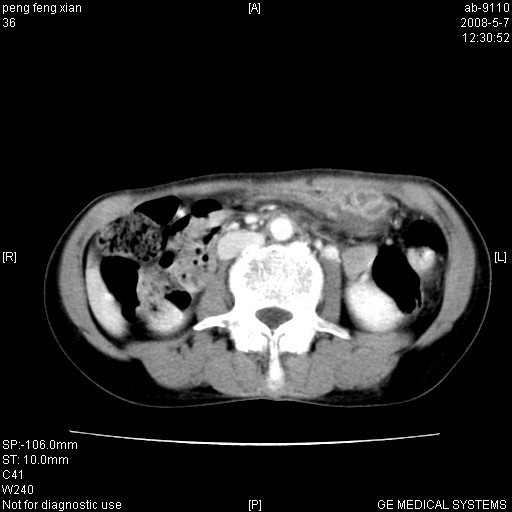

女,56岁。b超左一腹包块,考虑胃肠道肿瘤。

胃壁增厚,左前胸壁局限性隆起,考虑胃癌可能性大,建议做胃镜

典型胃癌胰体尾部受侵。

胃壁不规则增厚,考虑胃癌.应该多喝点水的.

胃体部胃壁增厚,不均匀性强化,与胰腺分解欠情.

考虑:胃癌,胰腺受侵待除外.

鉴别:胃淋巴瘤(强化不明显)

建议:胃镜检查.